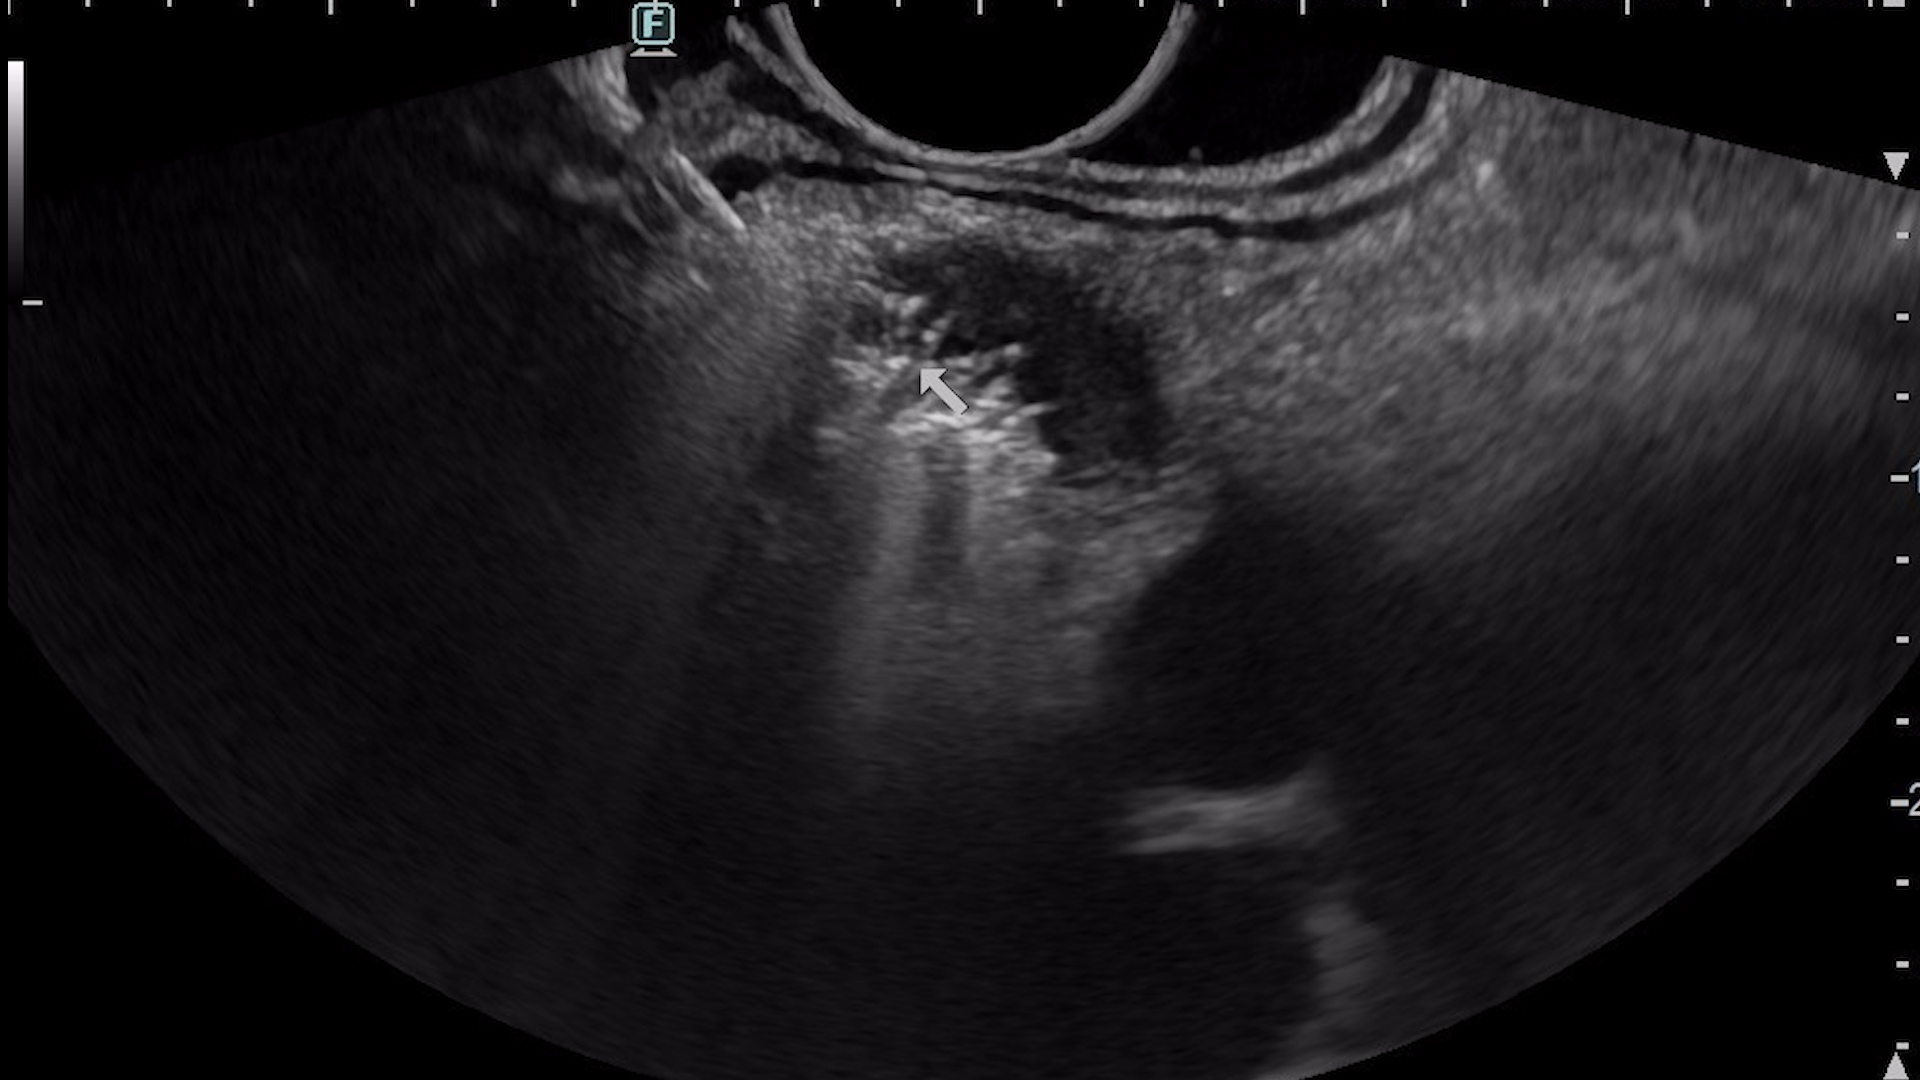

EUS-guided radiofrequency ablation was planned for treatment of the lesion (Fig. 5), using a 10 mm EUS-RFA catheter (Taewong). After probe insertion, the ablation cycle is started and a hyperechoic area of coagulative necrosis is seen over the RFA catheter (Fig. 6). The procedure was carried out in 3 passes, to fully ablate the lesion. Contrast-enhanced EUS, compared to pre-ablation hyperenhancement, revealed no uptake of contrast in the area of the pancreatic tumor (Fig. 7). The procedure was uneventful and the patient recovered very well and rapidly. Second day after the procedure, fasting glycemia rose to 82 mg/dL and in two weeks it reached 98 mg/dL.